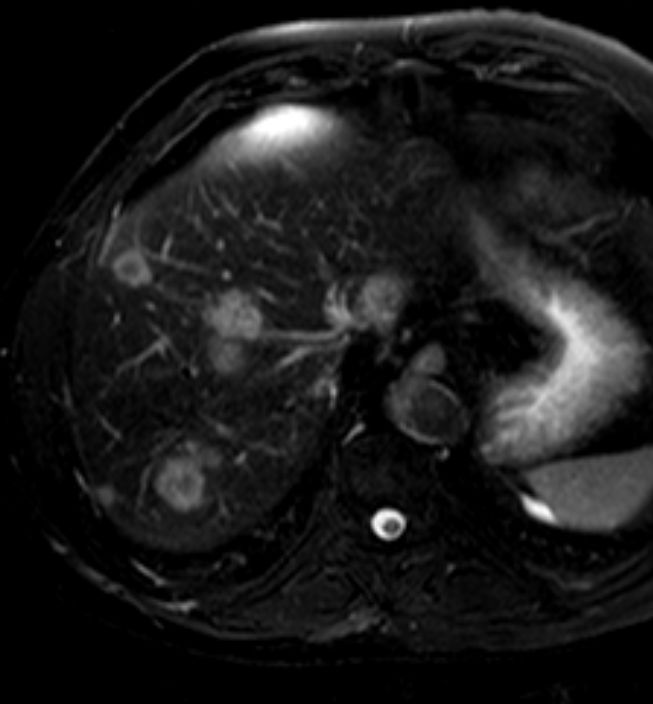

Lebermetastasen

Lebermetastasen bei Sigmakarzinom, MRT (T2W-Spiral, 3 Min. nach KM)